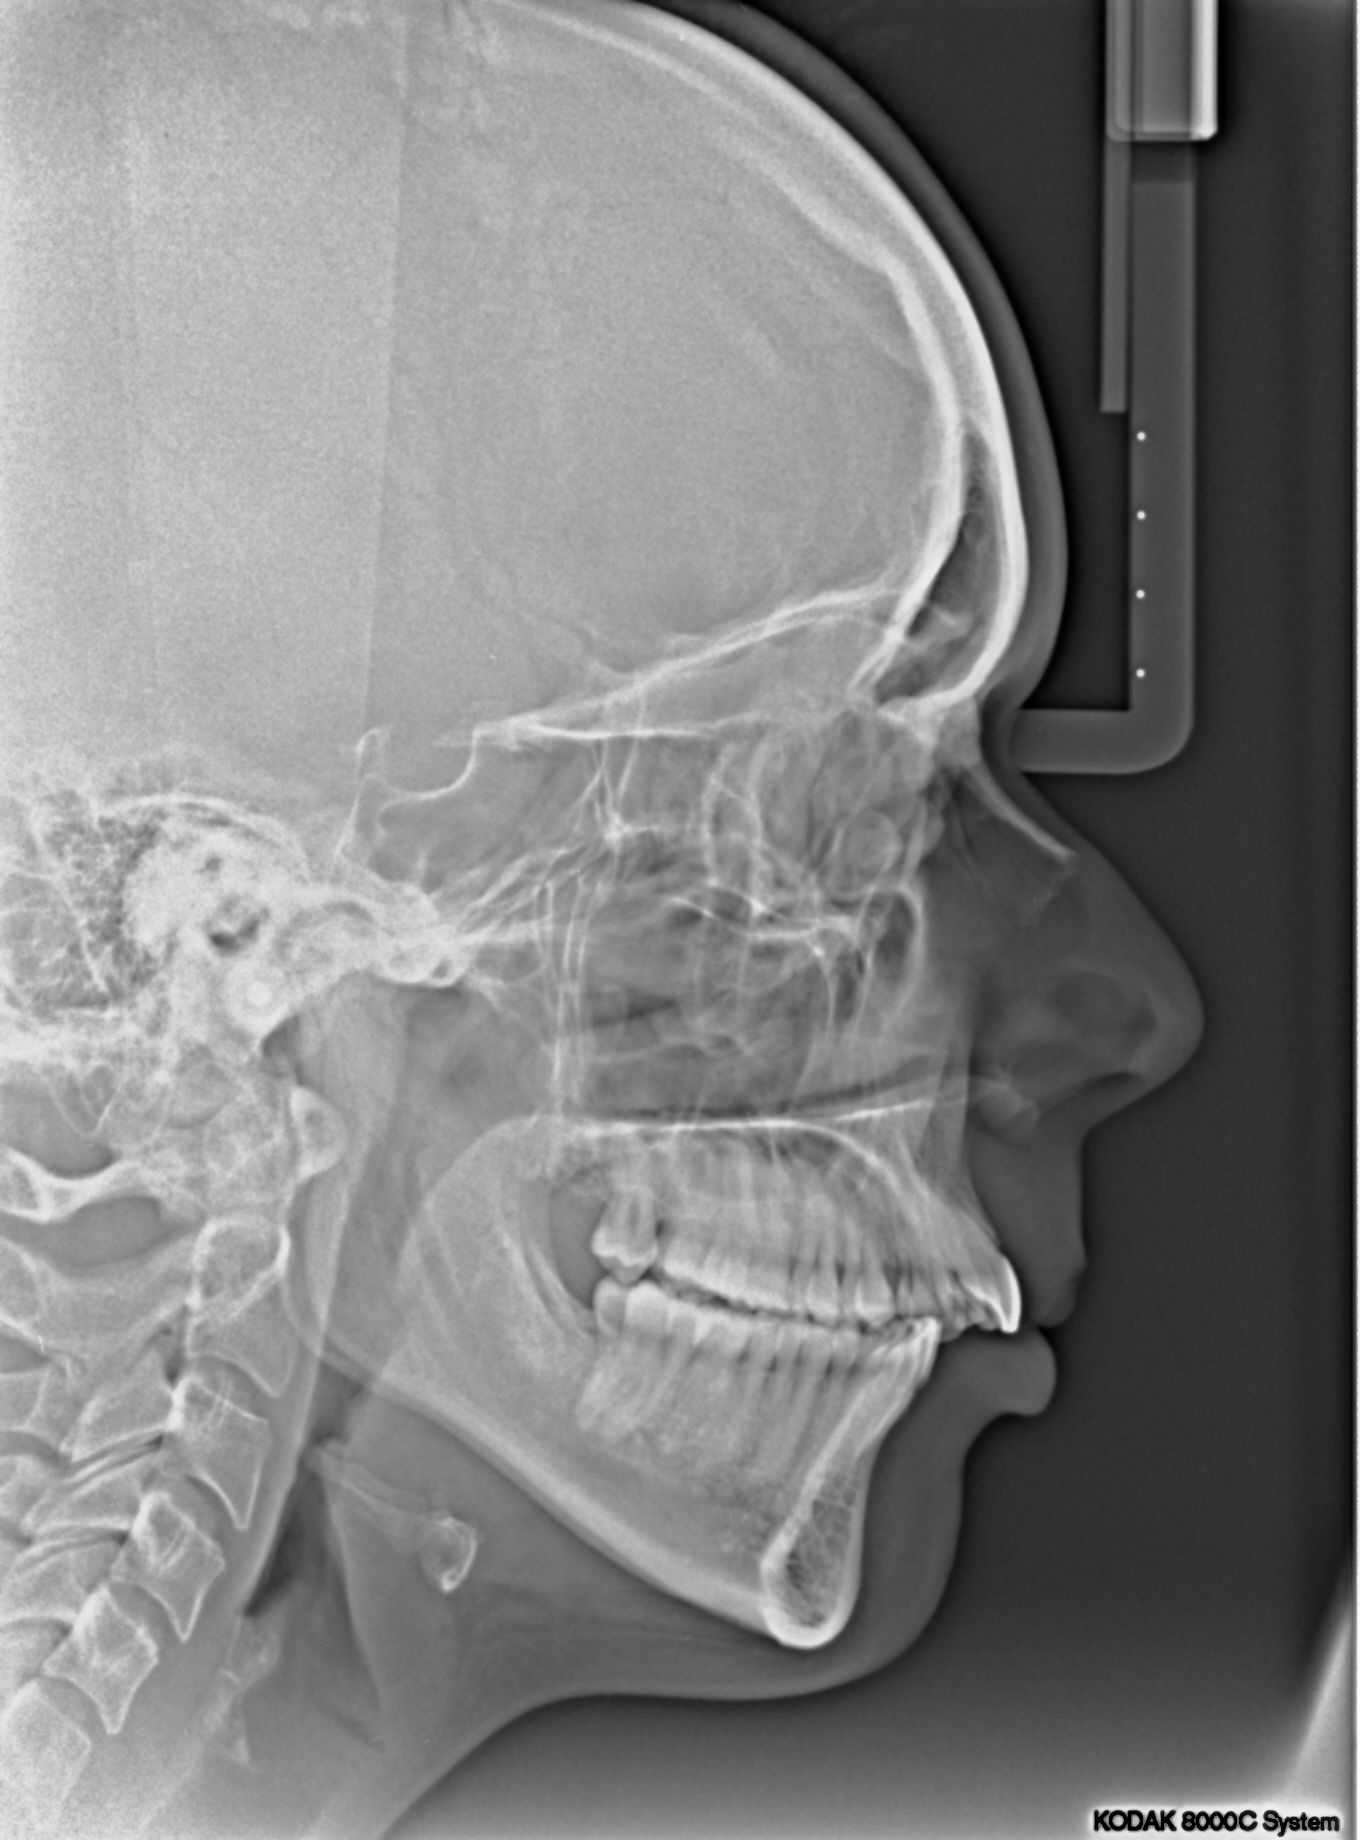

Als dit voor u bespreekbaar is, volgt eerst nog een vervolg-afspraak bij de orthodontist om ‘documentatie’ te maken. Dat betekent een scan van uw gebit, lichtfoto’s en röntgenfoto’s. De orthodontist zorgt ervoor dat de kMKA-chirurgen ook deze (röntgen)foto’s ter beschikking krijgen en laat de scan van het gebit uitprinten in 3D en neemt dat 3D model mee naar Frisius MC Leeuwarden.

Als de orthodontische voorbereiding voor de operatie ver gevorderd is, wordt de kaakoperatie door de kaakchirurgen digitaal gepland in 3D.

Met een prachtig digitaal planningsprogramma in samenwerking met het UMCG, wordt bepaald wat het mooiste resultaat geeft. Hieronder geven we voorbeelden van hoe zo’n planning er uit kan zien. In dit voorbeeld wordt de bovenkaak verplaatst, de onderkaak en de kin. Vaak kan de operatie ook beperkt worden tot alleen een onderkaak of alleen een bovenkaak. Het is maar net wat per specifiek geval de beste oplossing is.